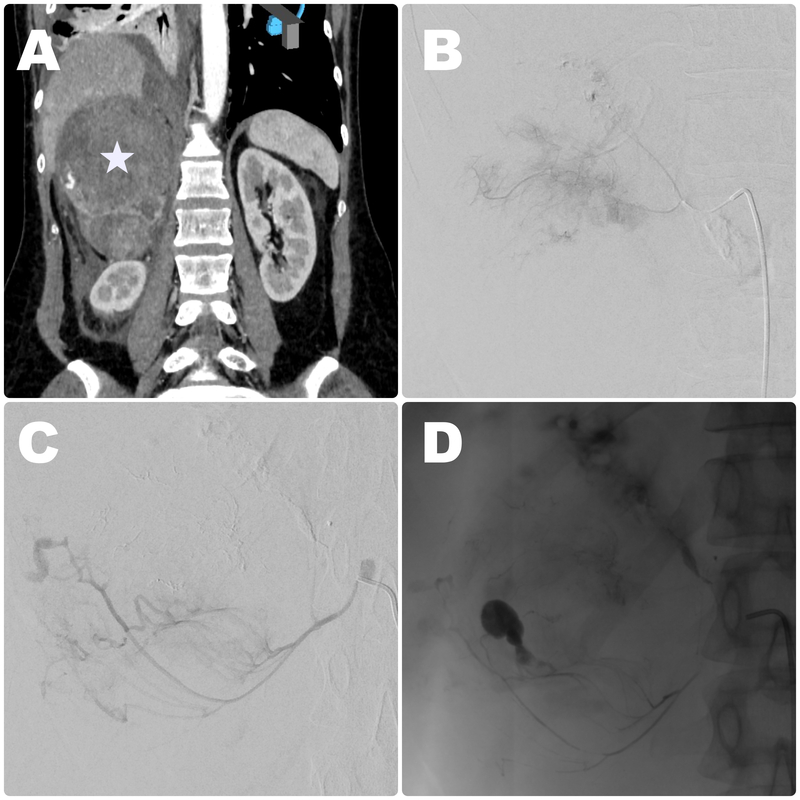

All procedures were carried out by an experienced interventional radiologist under local anaesthesia or conscious sedation from femoral access. Firstly, an aortic angiography from a 5 Fr diagnostic catheter positioned above the renal level was performed. Afterwards, possible culprit vessels (phrenic, renal, and adrenal arteries) were selectively catheterised and investigated. If signs of vessel injury (contrast extravasation, abnormal blush) were detected superselective catheterisation with a 2.7 Fr microcatheter was performed. Embolic agents were adopted according to the type of vessel lesion and operator’s preference. Control DSA was performed to confirm vessel occlusion. The puncture site was compressed or closed with a closure device. The typical endovascular procedure is presented in Figure 1.

Figure 1

Embolisation procedure in a 67-year-old male patient with metastatic lesion in a right adrenal gland originating from lung cancer with signs of haemodynamic instability due to haemorrhage. A) Baseline contrast-enhanced CT disclosed large right-sided lesion in an adrenal gland (white star) with visible contrast extravasation in the lower part. Intraprocedural contrast injection showed extraluminal blush (B), and signs of contrast extravasation (C) suggestive of active bleeding from upper and middle adrenal arteries. D) Control imaging obtained after embolisation with glue showed successful exclusion of the culprit vessels